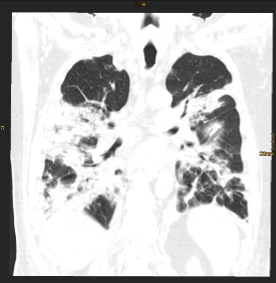

BU: CT Thorax eines Teilnehmers während des stationären Aufenthalts (Bild links) und nach einem Jahr (Bild rechts) im Vergleich. Die initial ausgeprägten Gewebsvermehrungen sind deutlich rückläufig, jedoch zeigen sich residuell noch feine lineare Verdichtungen in beiden Unterlappen.

Eine aktuelle, kürzlich im angesehenen Fachjournal Radiology veröffentlichte Ein-Jahres-Folgestudie des Teams um den Radiologen Gerlig Widmann liefert nun neue Erkenntnisse zum Verlauf von Lungenveränderungen in der Computertomographie (CT) nach COVID-19. „In unserer viergeteilten Kohorte* betreffend den Schweregrad des initialen Verlaufes waren bei mehr als der Hälfte der TeilnehmerInnen auch noch zwölf Monate nach Krankenhausentlassung subtile Veränderungen im CT nachweisbar. Auch wenn eine Mehrheit dieses Anteils zumindest schwer erkrankt war, sind wir von diesem Ergebnis doch ein wenig überrascht. Der über 60-jährige männliche Patient mit kritischem Krankheitsverlauf trägt unseren Untersuchungen zufolge jedenfalls das größte Risiko, auch ein Jahr nach Covid-19 noch Lungenveränderungen im CT zu zeigen“, erklärt Radiologin und Erstautorin Anna Luger. Insgesamt wurden vier CT-Verlaufskontrollen der Lunge durchgeführt, von anfangs 142 ProbandInnen konnten nach einem Jahr noch 91 TeilnehmerInnen in die Studie eingeschlossen werden.

Im Detail zeigten 34 Prozent der TeilnehmerInnen oberflächennahe netzartige Verdichtungen der Lunge, geringe Milchglastrübungen oder beides, bei 20 Prozent der TeilnehmerInnen waren ausgedehnte Milchglastrübungen, oberflächennahe netzartige Verdichtungen, Bronchialerweiterungen und mikrozystische Veränderungen feststellbar, die eventuell auf Vernarbungsprozesse hindeuten. „Aus radiologischer Sicht lässt sich noch nicht abschätzen, wie sich diese strukturellen Lungenveränderungen zeitlich weiter verhalten“, so der Leiter der Radiologie in der interdisziplinären Studiengruppe, Gerlig Widmann. Drei Szenarien seien jedoch vorstellbar: Die Veränderungen bilden sich langsam vollständig zurück, die Veränderungen halten an und es entwickeln sich stabile Vernarbungen, oder das Lungengewebe wird zunehmend fibrotisch (Bindegewebsvermehrung) und es kommt begleitend zu kontinuierlich zunehmenden klinischen Symptomen. „In jedem Fall“, so Widmann, „werden wir den Verlauf gemeinsam mit unseren klinischen Partnern weiter wissenschaftlich begleiten“.